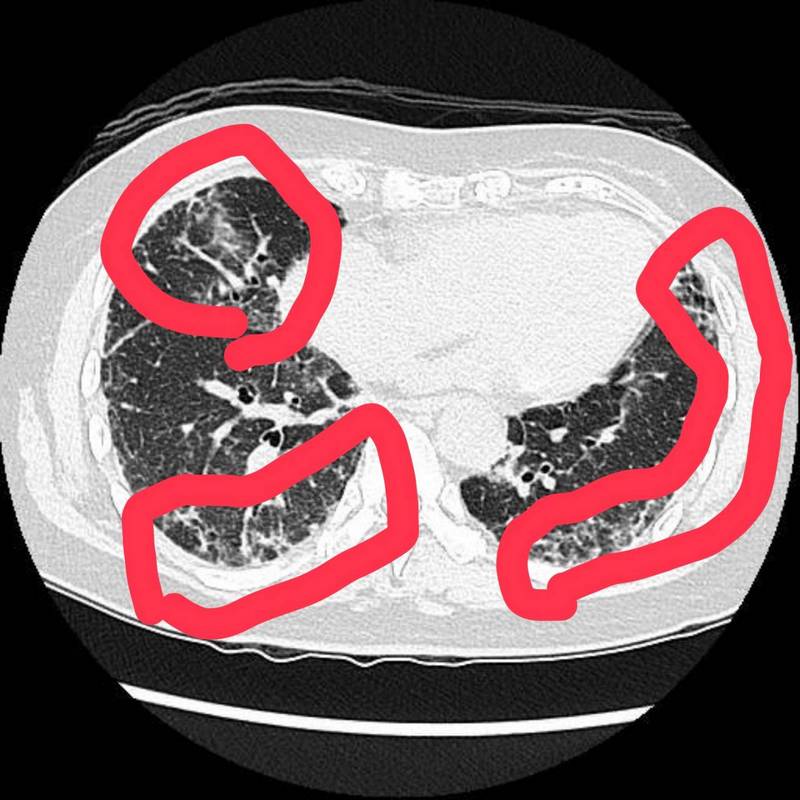

右圖:潘郁仁醫師表示,王女士電腦斷層影像顯示肺部出現白花花的纖維化症狀,初步診斷為間質性肺病。

年過八旬的王女士,長期有眼睛乾澀、口乾舌燥的困擾,最近因為連續數周咳嗽不止,來到花蓮慈濟醫院求診,經由胸腔內科醫師發現其呼吸聲異常,X光顯示肺部已嚴重浸潤,電腦斷層影像則顯示肺部出現纖維化症狀,初步診斷為間質性肺病,後續醫師謹慎地將王女士轉診至風濕免疫科,最後證實為發炎性自體免疫疾病「乾燥症」(修格連氏症,Sjogren's syndrome)。

潘郁仁醫師呼籲,乾燥症患者有口乾、眼澀症狀應該積極求診,越早治療越能減少對淚腺和唾液腺的損害,除了用藥物能改善症狀外,也能隨時注意是否有其他自體免疫疾病或併發症發生,例如更危險的肺部或腎臟病變。而王女士在接受適當的治療後,很快地就出院了,因為肺纖維化還在早期,使用藥物可以減緩惡化機會。